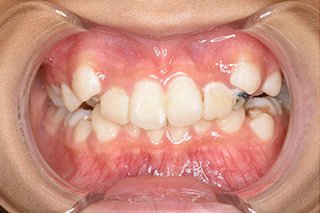

顎顔面矯正症例 11歳女児 Case

| 主訴 | 永久歯が変な所からはえてきている|顔貌 | |

|---|---|---|

| 施術内容 | 矯正1期治療 | |

| 治癒期間 | 1年5ヶ月間 | |

| 費用 | 459,200円(税込) | |

| リスク・ 副作用 | 痛みを伴う | |